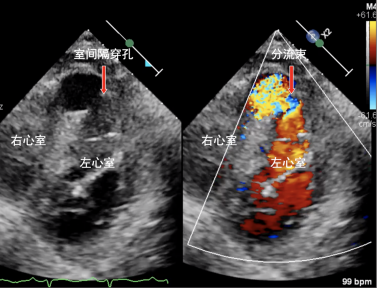

患者为92岁女性,入院前1周突发胸骨后闷痛,因胸痛程度不剧烈且症状自行缓解,误以为是胃肠道疾病,未予重视;后逐渐出现恶心、四肢乏力、气促、端坐呼吸等症状,由家属送至我院急诊科。急诊行心电图提示患者前壁心肌梗死,进一步完善心脏彩超见室间隔心尖段变薄、搏幅减低,探及大小约19mm回声失落,合并室间隔穿孔。

术前心脏彩超显示室间隔近心尖处穿孔及左向右分流束